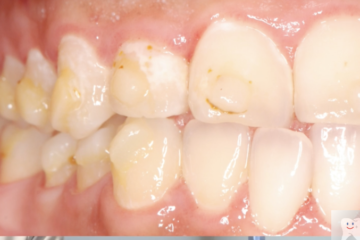

歯垢の付き方

ワイヤーの方が9倍多く歯垢が付く

脱灰の深さ

ワイヤー治療の方が3倍深く脱灰が進んでしまう

脱灰の面積

マウスピース治療の方が2倍広がる

ワイヤー矯正後

マウスピース矯正後